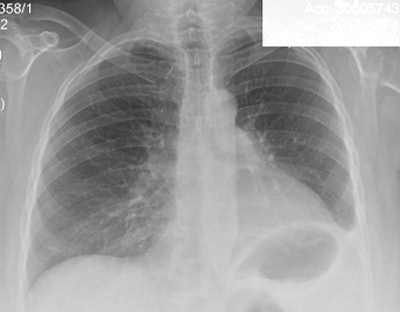

Lung cancer is clearly visible in the ultralow-dose CT image above but cannot be seen in the chest radiograph of the same patient below. All images courtesy of Dr. Waël Hanna.

Among the 311 patients enrolled, 1,096 pairs of x-ray and MDCT scans were analyzed, Hanna said. CT was significantly more sensitive than radiography (94% versus 21%, p < 0.0001) for the diagnosis of new or recurrent lung cancer. CT also had a higher negative predictive value than x-ray (99% versus 96%, p = 0.007).